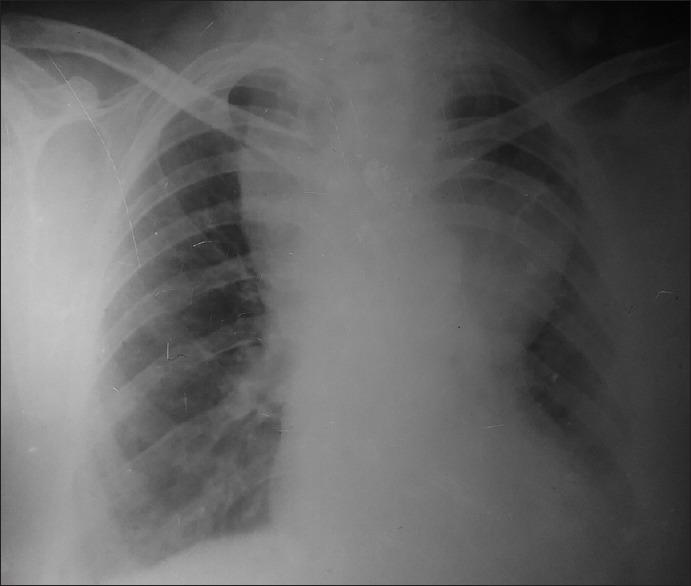

65-year-old Female with Cardiac Arrest and Return of Spontaneous Circulation.

Clin Pract Cases Emerg Med. 2018 Jul 18;2(3):181-186. doi: 10.5811/cpcem.2018.6.38420. eCollection 2018 Aug.